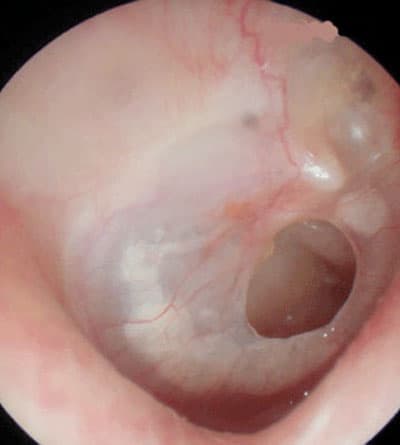

هناك عديد من الناس يوجد لديهم ثقب في طبلة الأذن الذي من شأنه إضعاف السمع, وتحدث هذه الثقوب في مختلف الأعمار, لكنها تزيد عند الأطفال، وطبلة الأذن هي عبارة عن غشاء رقيق يمكن السمع من خلاله في حالة كونه طبيعيا، وهو يقوم بفصل الأذن الخارجية عن الأذن الوسطى، ويقوم بحماية الأذن الوسطى من دخول الماء والأجسام الغريبة، إضافة إلى أهميته في تضخيم الأصوات الخارجية، لذلك فإن حدوث ثقب في طبلة الأذن يؤثر في السمع, ويعرض الأذن لالتهابات متكررة.

أسباب حدوث الثقب تكون في أكثر الأوقات نتيجة الالتهابات المزمنة في الأذن الوسطى, أو بسبب إصابات مباشرة في طبلة الأذن، ويتفاوت ضعف السمع حسب مساحة الثقب وموقعه من الطبلة، وما إذا كان مصحوبا بتلف في عظيمات الأذن الوسطى. وأعراض ثقب الطبلة تظهر في خروج صديد متكرر من الأذن وضعف في السمع.

الوقت المناسب لترقيع الأذن يكون بعد تشخيص الثقب, وعدم وجود التهاب في الأذن الوسطى, واستبعاد وجود خلل في قناة تهوية الأذن الوسطى (قناة استاكيوس)، وفي حالة الأطفال عند تجاوزهم مرحلة الالتهابات المتكررة.